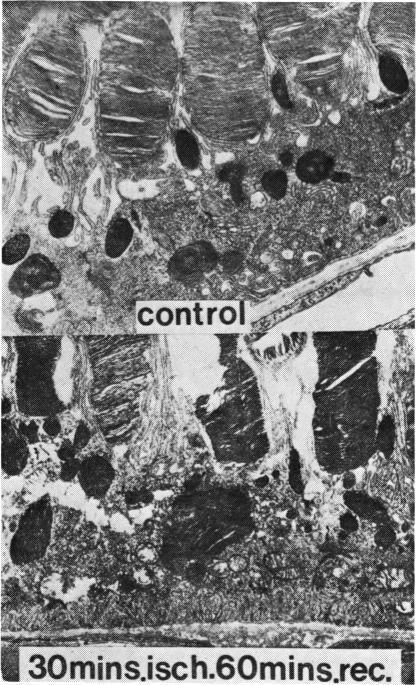

The interdependence of the outer retina and pigment epithelium is illustrated by the functional changes and structural alterations which occur in each in response to choroidal ischaemia, retinal detachment, vitamin A deficiency, and other causes. The pluripotential role of the pigment epithelium is stressed, particularly in relation to the phagocytosis of outer segment material and the ability of this layer to undergo metaplasia into a variety of different cell types. Similarities of all disturbances of the retinal-pigment epithelial interface to retinitis pigmentosa are pointed out, and the significance of the findings in relation to this disease is discussed.

外层视网膜与色素上皮之间的相互依存关系,体现在各自因脉络膜缺血、视网膜脱离、维生素A缺乏及其他病因所发生的功能变化和结构改变中。着重强调了色素上皮的多能作用,尤其是其对外节段物质的吞噬作用,以及该层发生化生成为多种不同细胞类型的能力。指出了视网膜-色素上皮界面所有病变与色素性视网膜炎的相似之处,并讨论了这些发现与该疾病的相关性。